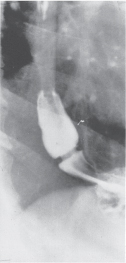

With the advent of clinical radiology, it became evident that a diaphragmatic hernia was a relatively common abnormality and was not always accompanied by symptoms. Three types of esophageal hiatal hernia were identified: (a) the sliding hernia, type I, characterized by an upward dislocation of the cardia in the posterior mediastinum (Fig. 25-8A); (b) the rolling or paraesophageal hernia (PEH), type II, characterized by an upward dislocation of the gastric fundus alongside a normally positioned cardia (Fig. 25-8B); and (c) the combined sliding-rolling or mixed hernia, type III, characterized by an upward dislocation of both the cardia and the gastric fundus (Fig. 25-8C). The end stage of type I and type II hernias occurs when the whole stomach migrates up into the chest by rotating 180° around its longitudinal axis, with the cardia and pylorus as fixed points. In this situation the abnormality is usually referred to as an intrathoracic stomach (Fig. 25-8D). In some taxonomies, a type IV hiatal hernia is declared when an additional organ, usually the colon, herniates as well.

When radiographic examinations are done in response to GI symptoms, the incidence of a sliding hiatal hernia is seven times higher than that of a PEH. The PEH is also known as the giant hiatal hernia. Over time the pressure gradient between the abdomen and chest enlarges the hiatal hernia. In many cases the type 1 sliding hernia will evolve into a type III mixed hernia. Type II hernias are quite rare. (See Schwartz 9th ed., p 842.)

FIG. 25-8. A. Radiogram of a type I (sliding) hiatal hernia. B. Radiogram of a type II (rolling or paraesophageal) hernia. C. Radiogram of a type III (combined sliding-rolling or mixed) hernia. D.Radiogram of an intrathoracic stomach. This is the end stage of a large hiatal hernia regardless of its initial classification. Note that the stomach has rotated 180° around its longitudinal axis, with the cardia and pylorus as fixed points. (Reproduced with permission from DeMeester TR, Bonavina L: Paraesophageal hiatal hernia, in Nyhus LM, Condon RE (eds): Hernia, 3rd ed. Philadelphia: Lippincott, 1989, p 684.)